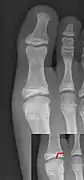

Salter–Harris III fracture of big toe proximal phalanx.

Salter–Harris IV fracture of big toe proximal phalanx.